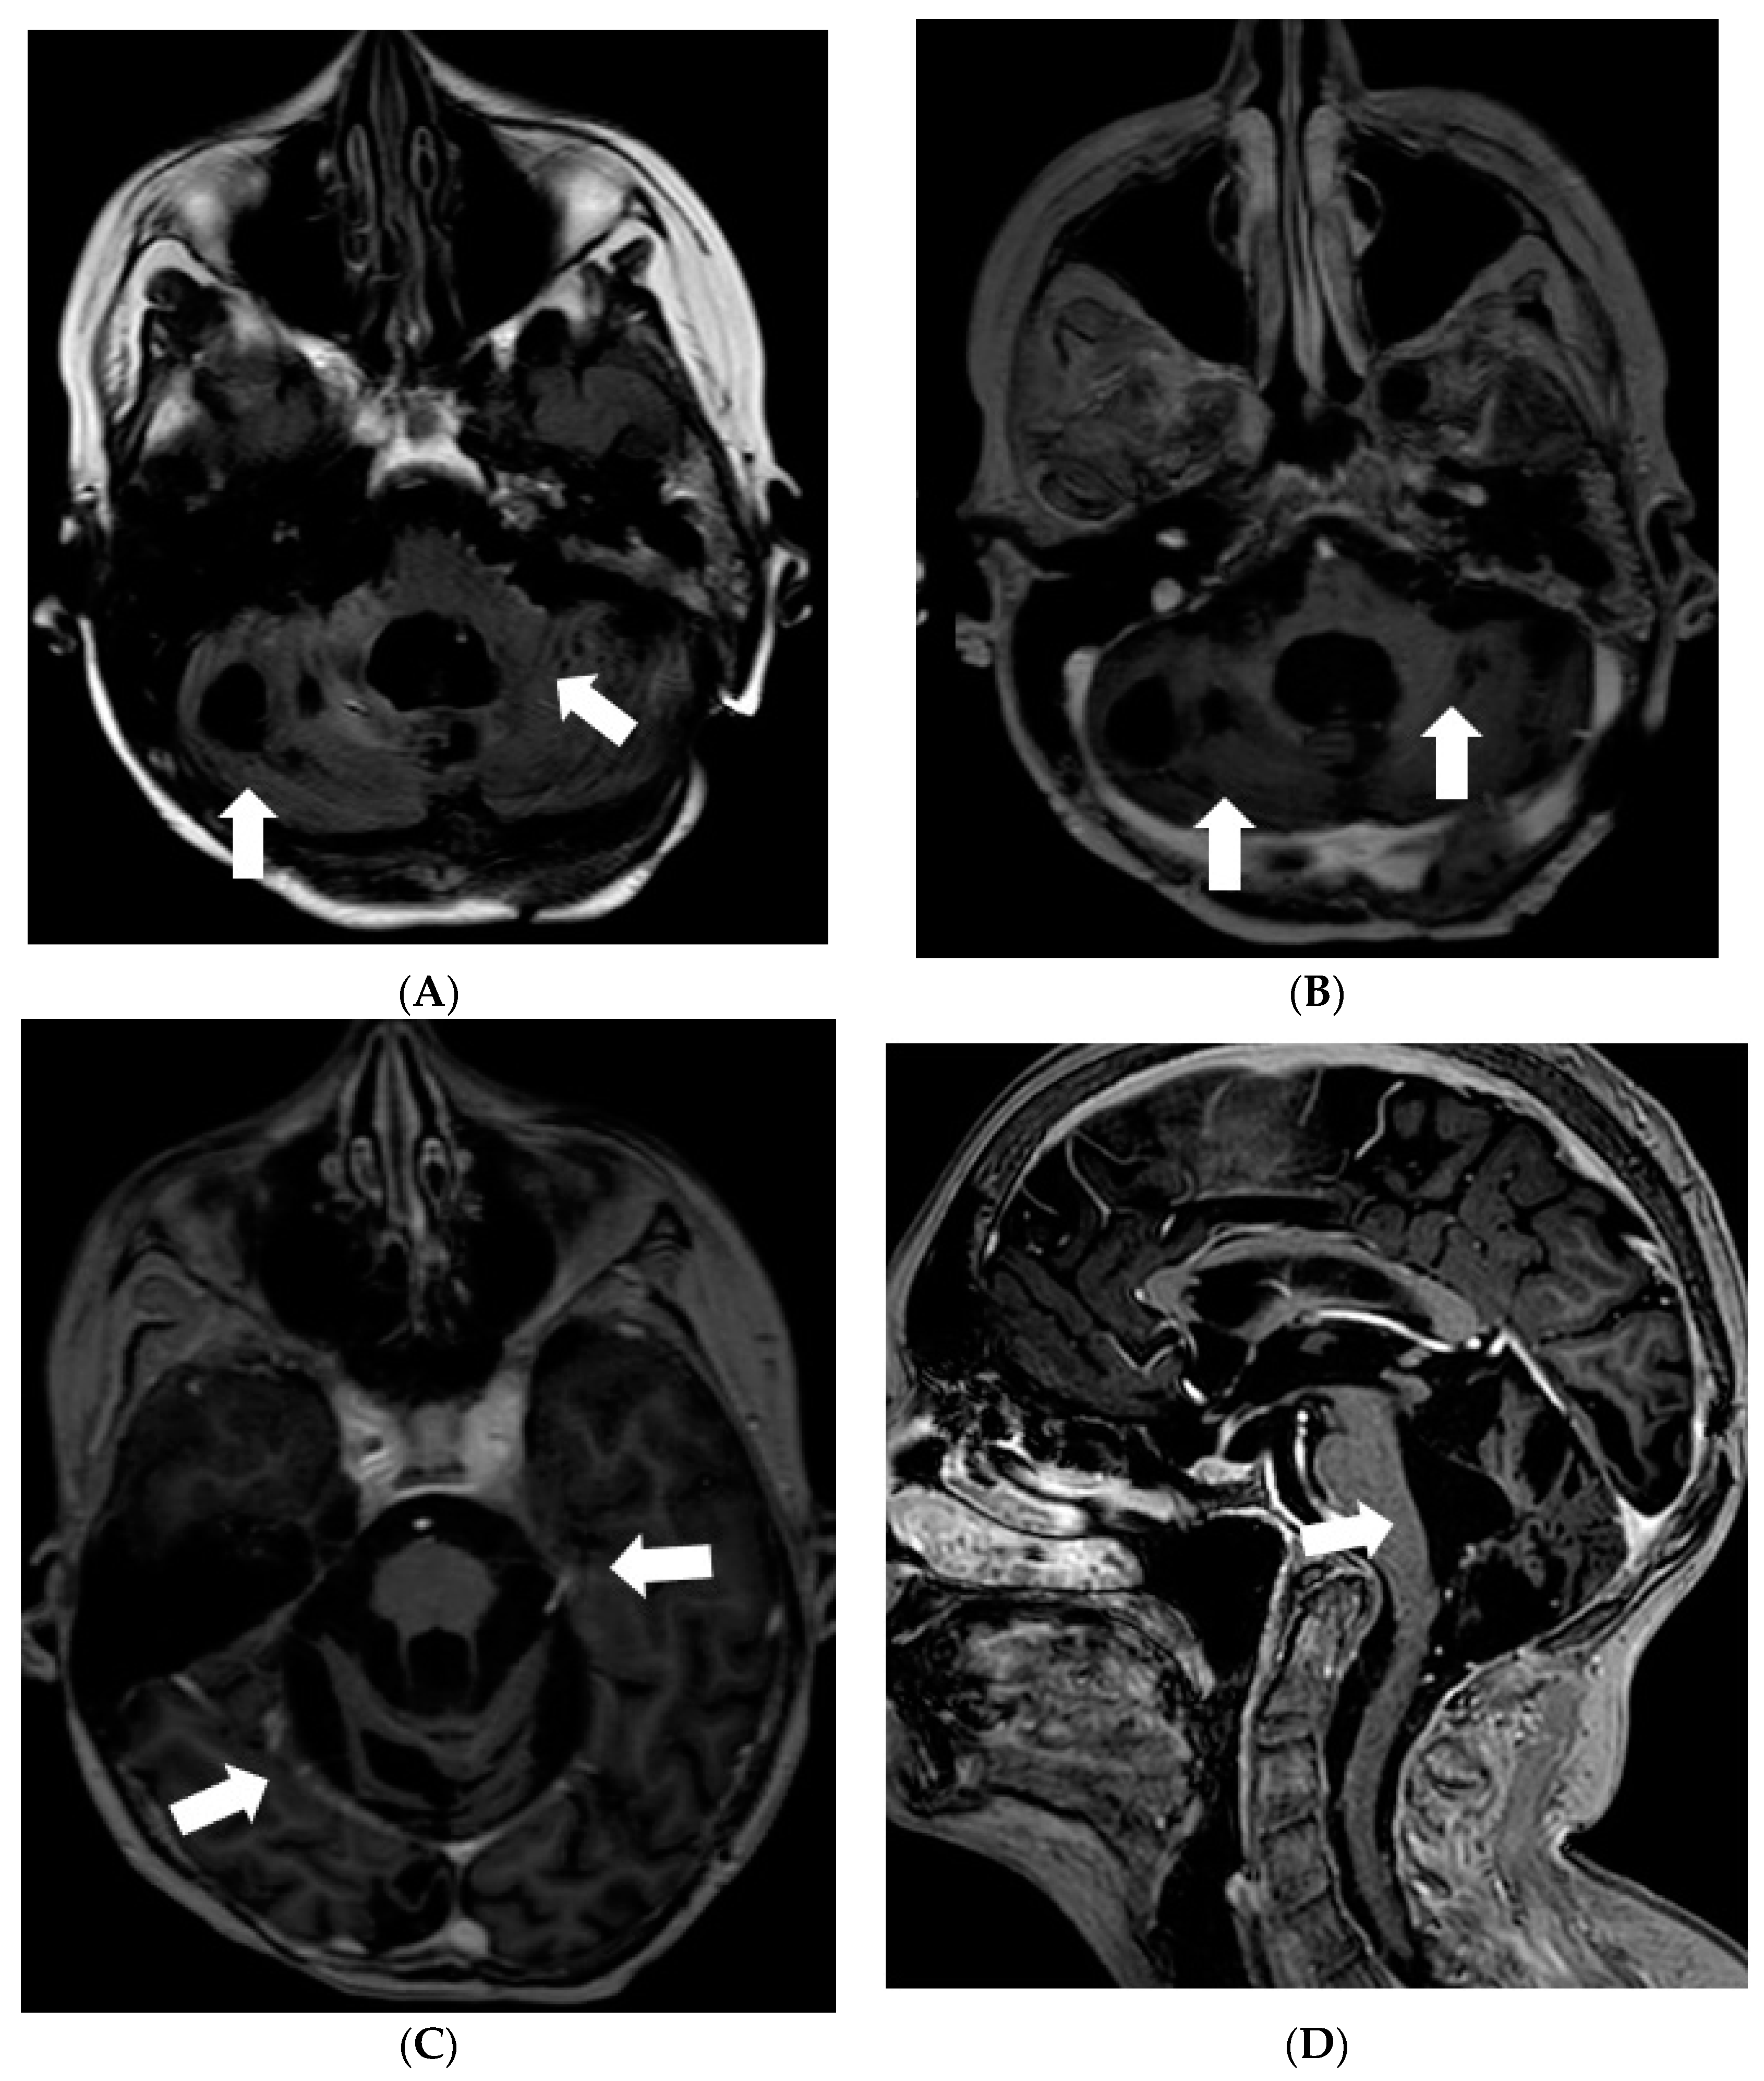

After 4 months when symptoms of raised intracranial pressure recurred, additional findings were detected on follow-up MRI. Most of the subarachnoid cisterns, Sylvian fissures, sulci of superior parts of the cerebellum, and the lower part of the fourth ventricle were filled with diffuse non-contrast-enhancing multiple small cyst-like lesions (Figure 3). These lesions were more evident on T2W/FLAIR and T2W/SPC images; T2W/FLAIR revealed iso/slightly hypointense lesions resembling cysts in the previously mentioned areas. The lesions did not show diffusion restriction or any significant compression of adjacent structures. Additionally, magnetic resonance spectroscopy of the lesion demonstrated lactate peak. Due to the uncertain origin of the findings, a biopsy of the newly detected tissue in the perimesencephalic cistern was performed. Histological appearance and immunohistochemical phenotype of the sample were the same as in the previous examination, consistent with subarachnoid spread.

Figure 3.

Follow-up MRI of the brain 1 year after the onset of the symptoms (April 2012): (A) Axial T2W/FLAIR/FS and (B) T2W/SPC images disclose masses composed of multiple small cysts in the subarachnoid cisterns, Sylvian fissures, and cerebellar sulci. There is no contrast enhancement (C) in the referred areas.

Later the girl was treated in Klaipeda University Hospital. In May 2013, a follow-up MRI demonstrated enlarged cystic lesions in the subarachnoid spaces with compression of the brainstem and the cerebellum and vivid leptomeningeal enhancement extending to the spinal canal (Figure 4). T2W/FLAIR/FS images revealed heterogenous, slightly hyperintense lesions with hypointense foci in the subarachnoid spaces. Clinically, ataxia and weakness of the legs worsened. Partial resection of the neoplastic masses from premedullary cisterns and the IVth ventricle was performed. It was decided to administer chemotherapy with temozolomide. Gradually, the condition of the patient improved.

Figure 4.

Follow-up MRI of the brain 2 years after the onset of symptoms (May 2013): (A) Axial T2W/FLAIR/FS, (B) axial, and (C) sagittal T1W postcontrast images demonstrate enlarged cystic lesions in the subarachnoid spaces causing compression of the brainstem and the fourth ventricle and vivid leptomeningeal enhancement extending to the spinal canal.